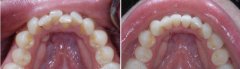

牙齿拥挤怎么治疗?

牙齿拥挤在生活中很常见,不仅会影响人的容貌,还会影响人的交际,所以牙列...【详细】

不同情况的牙齿拥挤怎么矫正?

牙齿拥挤让人的形象受损,让人感觉很尴尬,给生活带来很多不便,在现代每个...【详细】